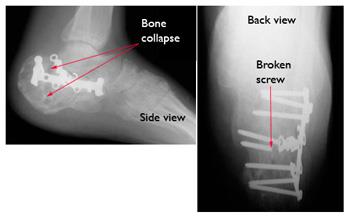

Hardware failure after fixation for calcaneus (heel bone) fracture

Six months after surgery, this patient's hardware has failed. Several screws have broken and the calcaneus has collapsed. This patient required major reconstruction, and today walks with a limp and has little motion in the foot.